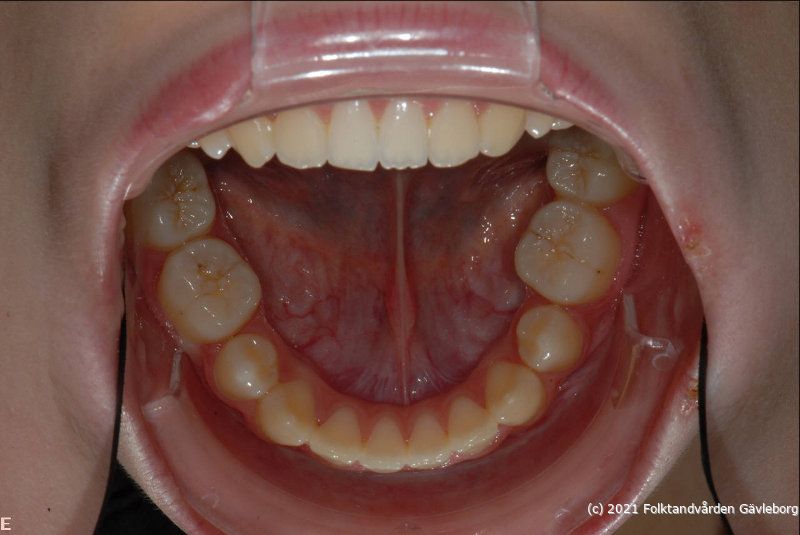

• uk              -  ”   -

• io05Underkäken